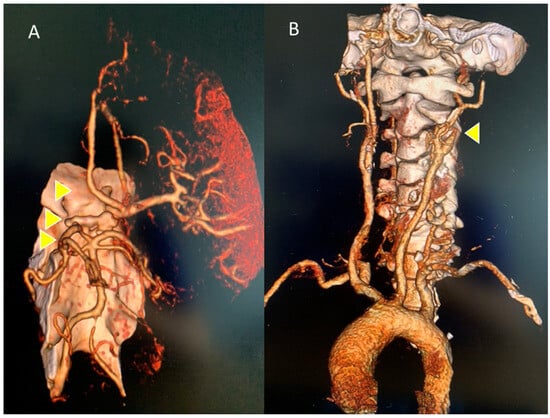

CT angiography of the epiaortic and intracranial arterial vessels showed a lack of opacification of the left internal carotid starting from a few millimeters after its origin, and of the ipsilateral sylvian axis and the anterior cerebral artery, with a poor collateral circulation of compensation. The perfusion angio-CT documented hypoperfusion, with a delay in the TTP at the fronto-insulo-parietal and left nucleocapsular site, in which an almost equivalent area of reduced MTT and CBV was inscribed, as per the ischemic core, and poor MTT/CBV mismatch, are is shown in Figure 2A and Figure 2B, respectively.

Figure 2. Intracranial and epiaortic angio-CT: (A) left anterior circulation occlusion: intracranial internal carotid, middle cerebral (MCA), anterior cerebral arteries; (B) lack of opacification on the left of the internal carotid artery a few mm from the origin. Thrombotic occlusion areas are indicated by yellow arrows.